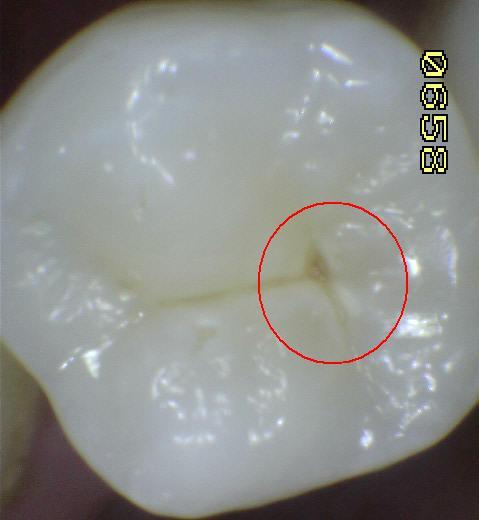

1. ICDAS 0

1. OPACIDAD CAFE

1. HALLAZGO CLINICO:confinada a la fisura

1. opacidad café cariosa visiblemente confinada a la fisura

1. 1B

2. HALLAZGO CLINICO mas alla de la fisura

1. opacida cafe cariosa, mas alla de la fisura

1. 2B

2. TRATAMIENTO

1. promoción y prenvención

1. topificación de fluor

2. DIAGNÓSTICO

1. Iesión cariosa no cavitacional

2. OPACIDAD BLANCA

1. con secado de aire

1. humeda na hay evidencia de cambio de color o caries, pero despues de secar se hace visible una opacidad blanca

1. 1w

2. sin secado de aire

1. opacidad blanca cariosa visible en seco, persida integridad esmalte

1. 2w

2. DIAGNOSTICO

1. lesión cariosa no cavitaacional

1. promoción y prevención

1. Topificación de flúor

2. PERDIDA DE LA INTEGRIDAD DE LA SUPERFICIE

1. HALLAZGO: macha café con presencia de cavidad

1. CRITERIO DE DIAGNOSTICO: despues de secar por 5 sg, existe una pérdida de integridad superficial sin exposición de dentina

1. DIAGNOSTICO

1. ICDAS 3